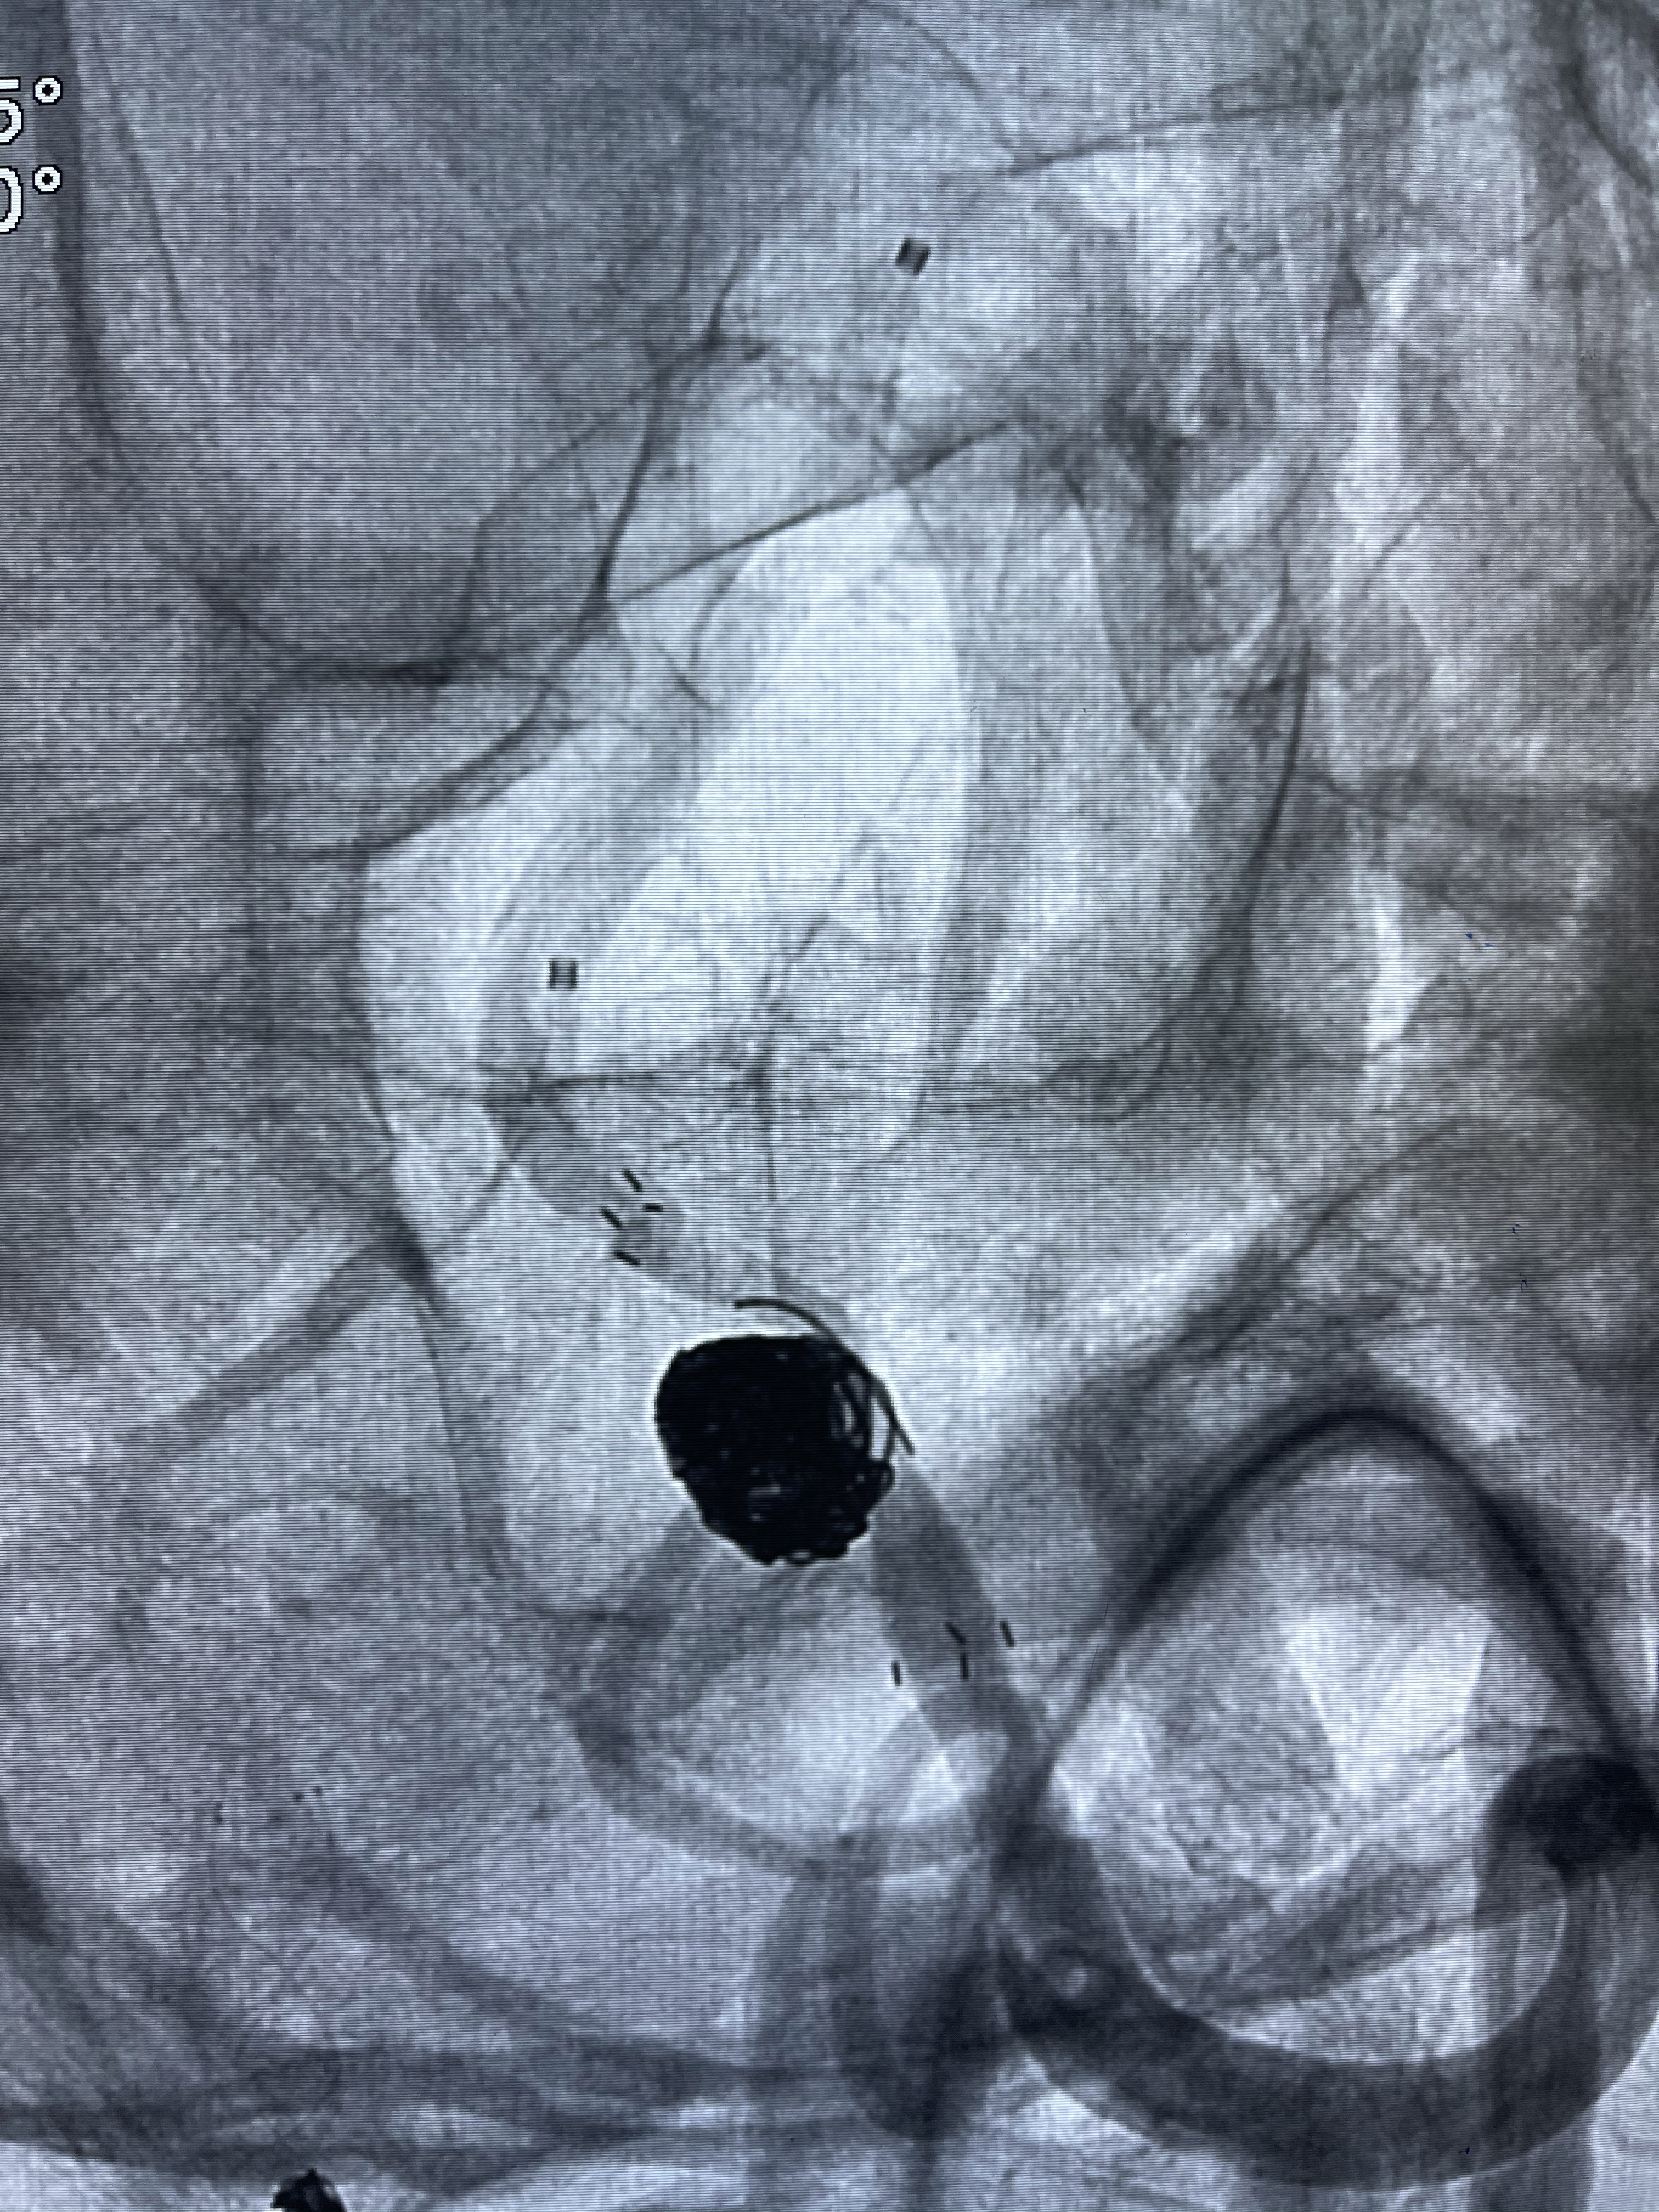

DA导引导管到位

工作角度造影

Eterprise4.0-23mm支架导管到位

Echelon10 45°角微导管塑形后到位

8mm-40cm微弹簧圈成篮

即刻造影